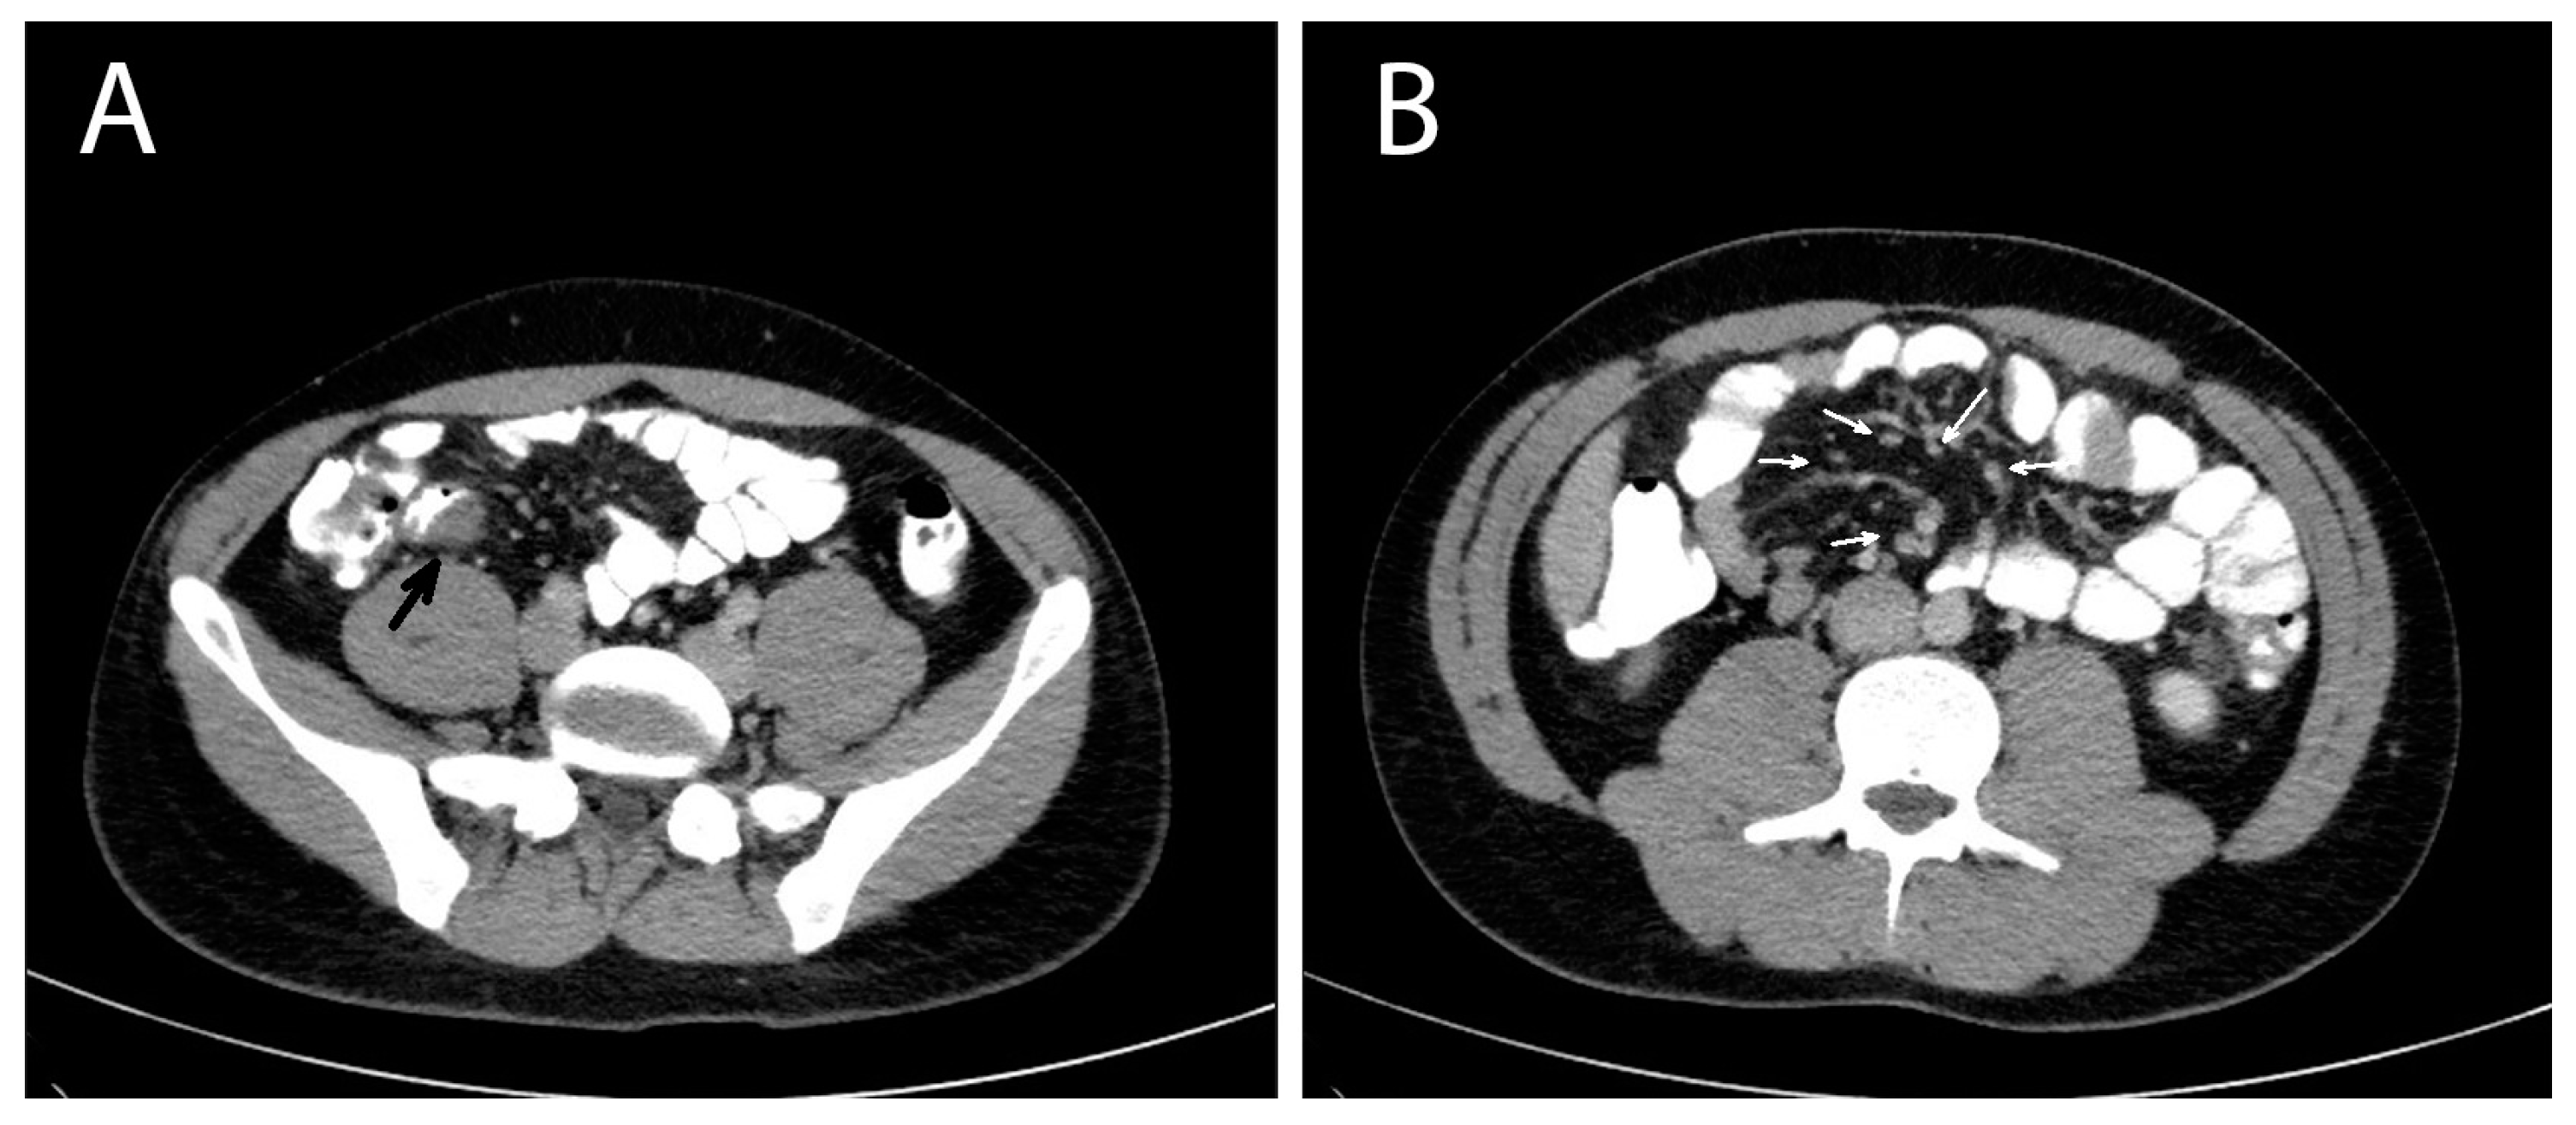

A contrast-enhanced computed tomography (CT) of the abdomen was performed the next day that showed multiple masses with soft tissue densities at the gastrocolic ligament (max ~1.1 cm), the left part of greater omentum (max ~1.5 cm), right paracolic gutter (max ~0.7 cm) and the left pararenal space (max ~1.7 cm), with multiple enlarged mesenteric lymph nodes along the ileocolic vessels (max ~1 cm), and at the aortic hiatus of the diaphragm (max ~1.2 cm). A thickening at the wall of the distal ileum right before the ileocolic junction was also depicted (Figure 1). The CT findings suggested a neoplastic disease and endoscopy of the upper and lower gastrointestinal tract was decided on. The oesophagogastroscopy was normal and a colonoscopy revealed a mild oedema of the mucosa of the distal ileum and a sessile polyp of the distal sigmoid. The investigation was completed with a computed tomography (CT) scan of the thorax, which was normal, and a contrast-enhanced MRI of the abdomen that depicted the same nodules and enlarged lymph nodes showed in the CT scan, in addition to a small quantity of pelvic fluid (ascites). During the investigation, the patient remained afebrile and hemodynamically stable, with, however, persistent abdominal symptoms and signs.

Considering the abovementioned findings, the young age of the patient and the absence of a definitive diagnosis, a diagnostic laparoscopy was performed, revealing a dilated terminal ileum with localized oedema and a firm round nodule of ~1 cm in diameter in the mesenteric border of the distal ileum, about 2 cm from the ileocolic junction. Many enlarged lymph nodes were found along the ileocolic and middle colic vessels and the greater omentum. Another firm nodule was found in the mesocolic border of the descending colon approximately 2 cm in diameter (Figure 2). There were no signs of diffuse peritoneal disease. Neoplasia was suspected and the operation converted to an open laparotomy through which an extended right colectomy and an omentectomy were performed. A side-to-side ileotransverse anastomosis re-established the continuity of the gastrointestinal tract. The nodule of the descending colon was also excised. The patient had an uneventful course and was discharged on postoperative day 13.

Figure 1. Abdomen contrast-enhanced MRI of a patient with invasive intestinal anisakiosis. (A): Distal ileum lesion (black arrow). (B): Multiple lymph nodes along ileocolic vessels (white arrows).